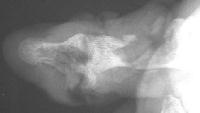

Circumferential router injury...